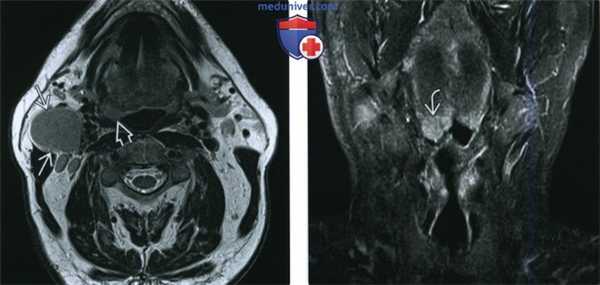

(Слева) При аксиальной КТ с КУ в левой половине шеи визуализируется большое однокамерное кистозное образование, имитирующее кисту второй жаберной щели по своему расположению. Обратите внимание на объемное образование в области нижнего полюса левой небной миндалины.

(Справа) При аксиальной КТ с КУ на более каудальном уровне визуализируется кистозно-некротическое объемное образование, расположенное снаружи от сонного влагалища, сзади от поднижнечелюстной слюнной железы спереди и изнутри от грудино-ключично-сосцевидной мышцы. Объемное образование напоминает кисту второй жаберной щели, но представляет собой метастаз ВПЧ(+) ПКР миндалины в лимфоузел.

(Слева) При МРТ Т2ВИ в аксиальной проекции визуализируется патологически измененный солидный лимфоузел уровня IIА. Определяется также неявное асимметричное утолщение миндалины, которое, хотя и может быть вариантом нормы, но при отсутствии других изменений, которые могли бы объяснить лимфаденопатию, позволяет порекомендовать биопсию.

(Справа) При МРТ Т2ВИ FS в корональной проекции у этого же пациента определяется гиперинтенсивный сигнал в язычной миндалине справа. Несмотря на то, что асимметрия укладывается в границы нормы, злокачественная лимфаденопатия делает ее подозрительной находкой. В итоге подтвердился ВПЧ(+) ПКР язычной миндалины.